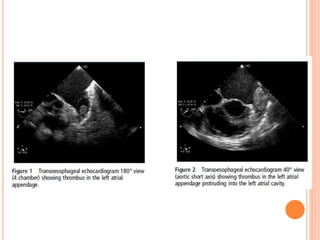

 Ia (thrombus confined to LAA)

 Ib (thrombus in LAA and protruding into LA cavity)

 IIa (attached to LA roof but above the plane of fossa ovalis)

 IIb (reaching below plane of fossa ovalis)

CLASSIFICATION  The thrombusin the left atrium can be classified as (Manjunath et al.) -  Ia (thrombus confined to LAA)  Ib (thrombus in LAA and protruding into LA cavity)  IIa (attached to LA roof but above the plane of fossa ovalis)  IIb (reaching below plane of fossa ovalis)  III (attached to interatrial septum)  IV (mobile with attachment to roof or lateral wall)  V (ball valve thrombus)